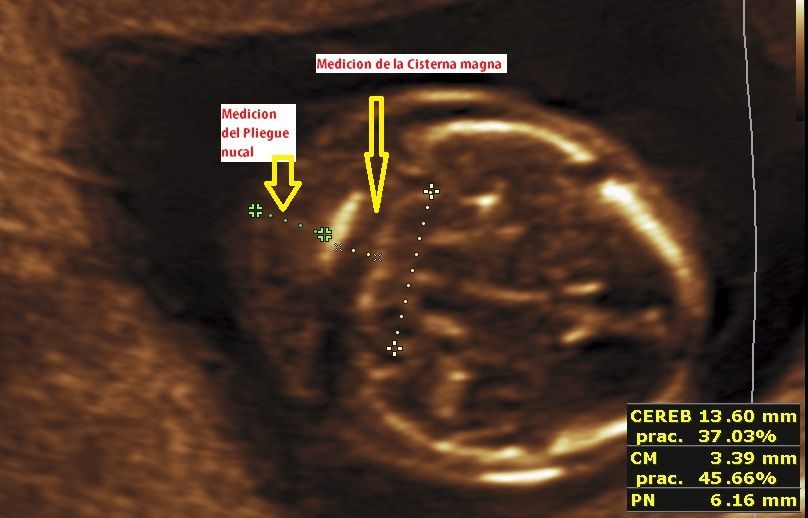

Realizamos las ecografías de viabilidad del embarazo, genética, morfológica, de bienestar fetal, ecocardiografías fetales, así como procedimientos invasivos como biopsia de vellosidades coriales y amniocentesis.